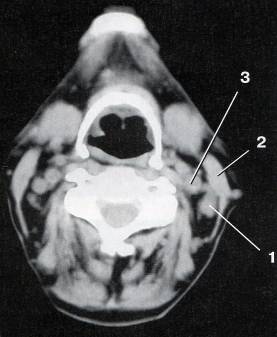

Компьютерная томография проводилась на аппарате Somatom AR. SHP, Siemens (ФРГ), шагом 3 мм в прямой и аксиальной плоскости, с последующей мультипланарной и трехмерной реконструкцией зоны интереса. Для КТ-исследования шеи предпочтительнее прямая сканограмма, на которой хорошо видна бифуркация трахеи, служащая ориентиром при планировании исследования (рисунок 3).

Для получения аксиальных сканов начальным уровнем сканирования служит уровень слуховых проходов, конечным – уровень бифуркации трахеи.

Рисунок 3 – Компьютерная томограмма шеи

1 – метастаз рака корня языка в яремно-двубрюшный лимфатический

узел; 2 – кивательная мышца; 3 – внутренняя сонная артерия.